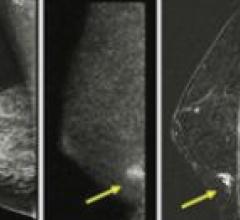

January 11, 2019Supplemental screening with ABUS helps personalize breast care for women with dense breasts and offers advanced clinical confidence for radiologists. ABUS can play an important role in early diagnosis of small, node negative, invasive cancers. Hear from Georgia Giakoumis Spear, M.D., from NorthShore University HealthSystem in the Chicagoland Area of Illinois as she speaks with Lucas Delaney, general manager for ABUS at GE Healthcare. As an early adopter of ABUS, she discusses the clinical need and her results with ABUS. She also provides her impressions of the newly introduced Invenia ABUS 2.0, and demonstrates a case utilizing the coronal view.

March 27, 2015Dense breast tissue can mask the appearance of tumors and limit the performance of mammography. When used as an adjunct to mammography, Invenia ABUS from GE Healthcare has been shown to improve invasive breast cancer detection by 55% over mammography alone.